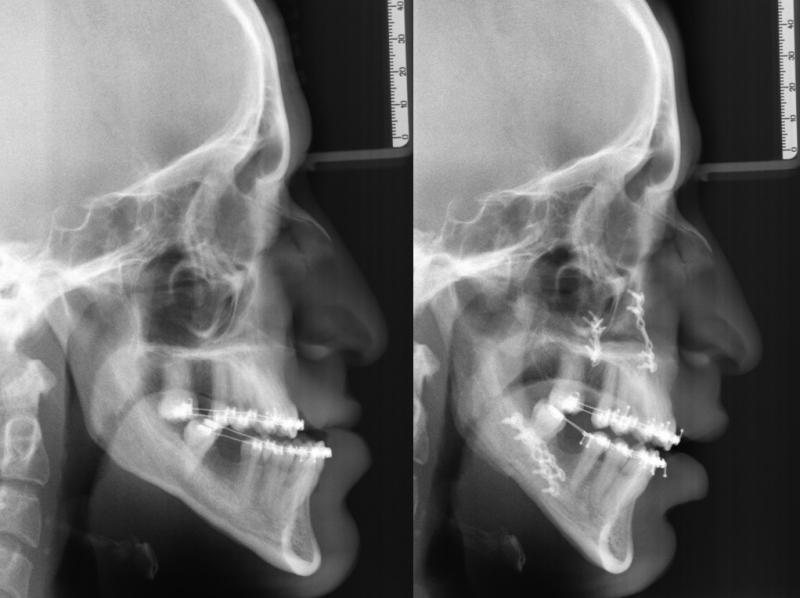

Diagnosis and treatment of dysgnathia, and orthognathic reconstructive surgery, genioplasty, maxillo-mandibular advancement/set-back, and surgical correction of facial asymmetry (See Images Below)

Orthognathic Surgery (Class II)

Orthognathic Surgery (Class III)

Orthognathic Surgery (Class II with 'Gummy Smile')